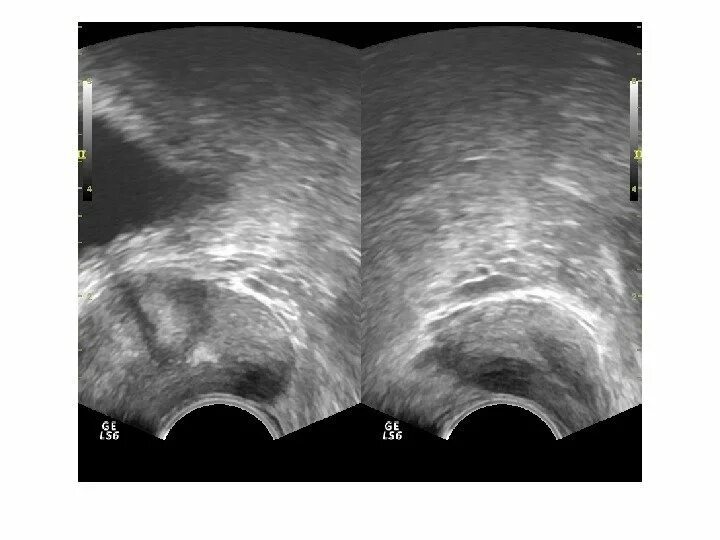

Фиброзные изменения предстательной железы